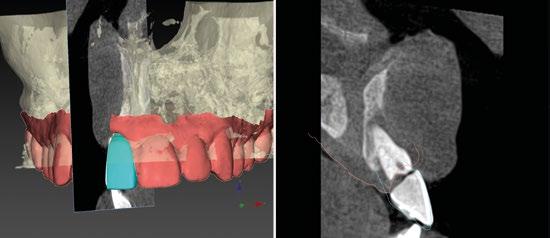

En el caso de obtener suficiente torque, podríamos incluso valorar la opción de cargar dicho implante. En este caso lo que hacemos es planificar también un pilar con el fin de trabajar nuestra prótesis a nivel gingival, siguiendo la filosofía de “One Abutment-One Time (OAOT)”.

Lo realmente extraordinario de este software de diagnóstico y planificación es que en una sola imagen tenemos total control de la posición de nuestro implante y de nuestro pilar, en función del hueso de la encía y de la futura restauración. Por lo tanto vamos a realizar una implantología protética, y biológicamente guiada. (Figura 10)